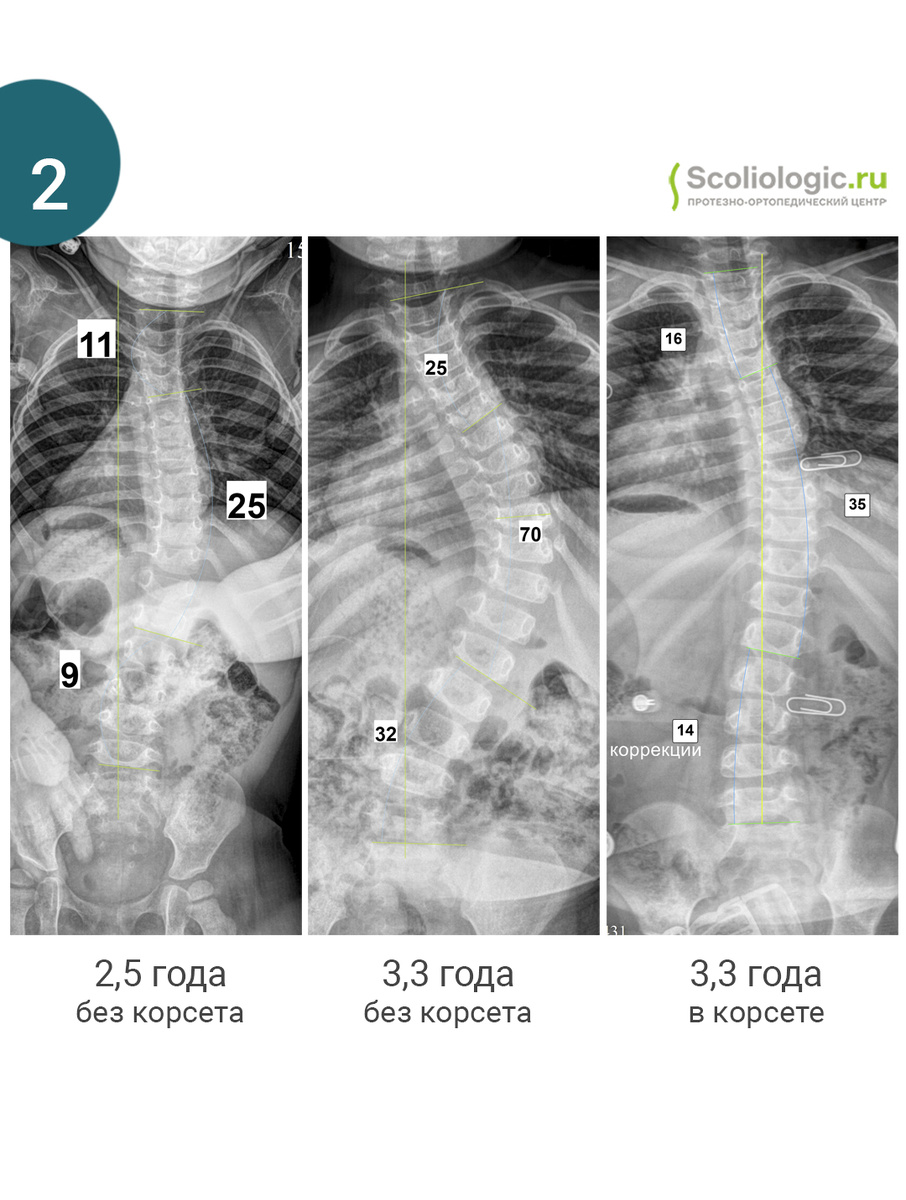

2. Синдром Прадера-Вилли. Одним из последствий является сколиоз. У такого сколиоза позвонки не ротрованы. Задача корсета – удерживать тело, помогать мышцам.